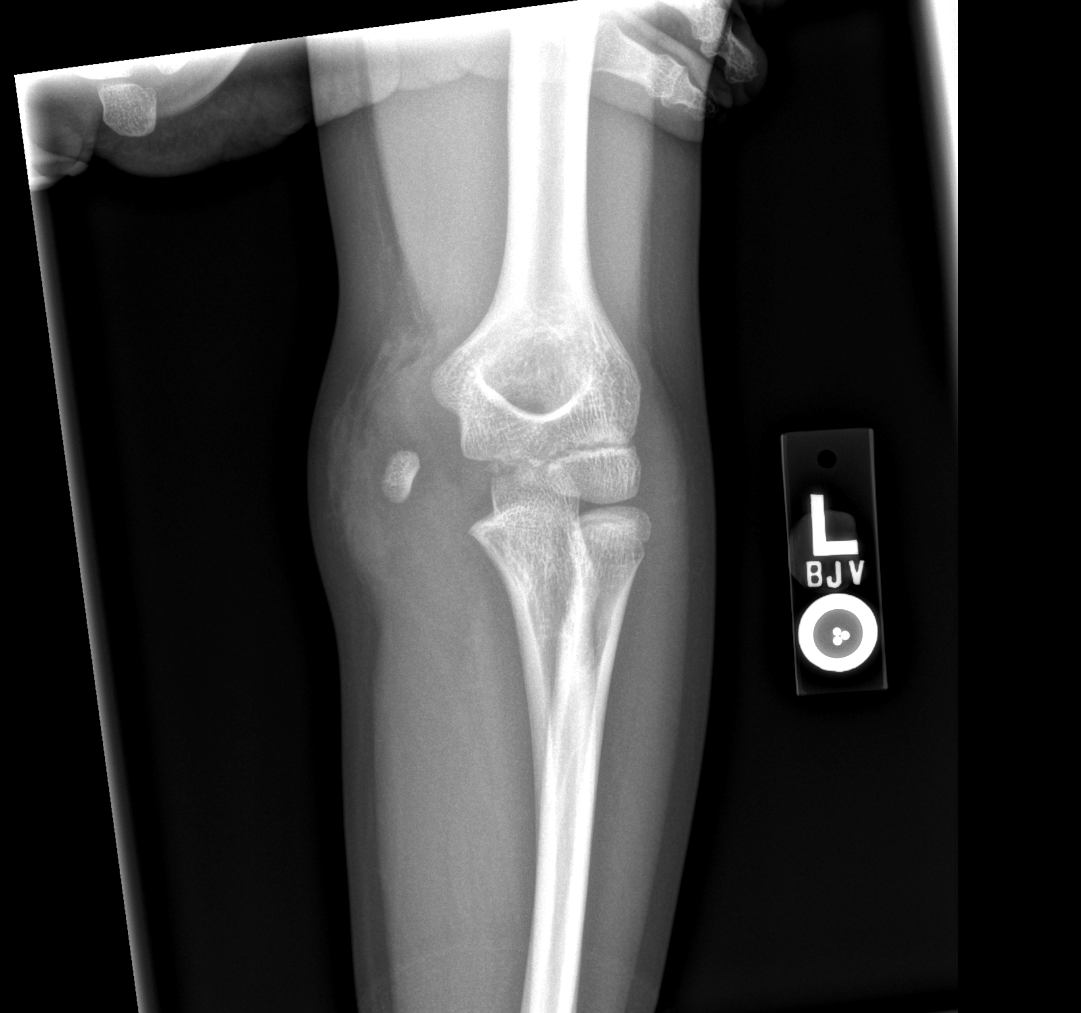

Info Images Findings Impression Reco/Acuity Case Images View Images / Launch Visage Case Notes History 2-month-old presents with decreased right arm movement, increased fussiness, and increased sleepiness for 2 days. Suspected non-accidental trauma. Exam Skeletal survey Prior Study none Dicom View Reference Material

Section 1 Submit Findings CB1550 Findings Skeletal Survey - Technique Check Skull AP/Lat Yes No Cervical and Thoracolumbar spine Yes No Chest X-Ray Yes No Ribs – Left/Right Oblique Yes No Abdominal X-Ray Yes No Pelvis with both hips Yes No Bilateral Humerus, Forearm, Hand Yes No Bilateral Femur, Tibia/fibula, feet Yes No Any additional lateral views of the extremities Yes No The exam is over or under penetrated. Yes No The exam may or may not be limited by overlying structures or soft tissues, body habitus, patient positioning, support devices, or motion. Yes No The area of concern is indicated by the patient, technologist, or care provider. Yes No The area of concern is included on the exam. Yes No Soft Tissues There is soft tissue swelling, indistinctness of fat/muscle planes, gas, or laceration in the area of clinical concern. Yes No There is an effusion, fat pad displacement, or fat fluid level. Yes No There is a radiodense or lucent foreign body. Yes No There are other densities, calcifications, post-surgical changes, or support devices in the soft tissues. Yes No Any support lines/tubes. Yes No Bone There is a break or interruption of the continuity of the cortical or cancellous bone. Yes No There is overriding of the trabeculae with apparent sclerosis. Yes No There is displacement of a fracture fragment. Yes No There is bowing of the bone in addition to the fracture at the apex of the bowed bone concerning for the greenstick. Yes No There is a spiral fracture of the leg concerning for toddler’s fracture. Yes No There is abnormal angulation or bulging of the cortical surface relative to the normal cortex which could be from a buckle or torus fracture. Yes No There is a displaced fragment which may be from avulsion by a tendon, ligament, or joint capsule or from a comminuted or other fracture. Yes No The stress trabeculae or other trabeculae of the cancellous bone are interrupted or otherwise abnormal. Yes No There is subperiosteal or endosteal reaction which could indicate a healing or subacute fracture or other abnormality. Yes No There is hard/soft callus formation. Yes No There is remodeling of the bone. Yes No There is a corner fracture or metaphyseal lesion that could be from nonaccidental trauma. Yes No There are multiple fractures of different ages. Yes No There are vertebral body/spinous process fractures. Yes No There are rib fractures. Location - posterior or lateral. Yes No There is scapular/sternal fracture. Yes No There are fractures of the digits. Yes No There are wormian bones. Yes No There are intrasutural bones. Yes No There is metaphyseal abnormality (lucencies, increased density, erosion) which may be from something other than injury such as stress, metabolic disease (e.g. rickets with loss or distortion of the zone of the provisional calcification), neoplasm (e.g. leukemia), heavy metals, inflammation, or infection. Yes No There are metaphyseal spurs. Yes No There are bony deformities involving multiple bones. Yes No The bones are gracile. Yes No There are non-healing fractures. Yes No There is/are focal or multifocal lytic/lucent, blastic/sclerotic or mixed density lesion(s) or other abnormality. Yes No Overall bone density is increased or decreased with or without thinning or thickening of the cortical or cancellous bone. Yes No Growth plates, ossification centers, apophyses The growth plate(s) is/are abnormal. Yes No There is widening of the physis from a fracture with or without displacement of the epiphysis (Salter-Harris I). Yes No There is a fracture through the physis which then extends into the metaphysis with or without angulation or displacement (S-H II). Yes No There is a fracture through the physis which then extends into the epiphysis and is intra-articular, with or without angulation or displacement (S-H III). Yes No There is a fracture through the metaphysis, physis, and epiphysis which extends into the joint space with or without angulation or displacement (S-H IV). Yes No There is narrowing of the physis from a compression fracture (S-H V). Yes No The apophysis, epicondyle, secondary ossification center, or accessory ossicle is displaced or otherwise abnormal. Yes No The ossification centers are underdeveloped. Yes No Joints and alignment There is an effusion, fat pad displacement, or fat fluid level. Yes No The epiphysis or subchondral bone is fractured, interrupted, flattened, compressed, impacted, displaced, or otherwise abnormal. Yes No There is an intra-articular loose body or chondrocalcinosis. Yes No The joint is widened, narrowed, dislocated, malaligned, or incongruent. Yes No There is pseudoarthrosis. Yes No Other findings There are developmental changes or other anatomic variants or other existing conditions that may or may not be contributing to symptoms which can or should be further evaluated non-emergently or are otherwise incidental. Yes No The remainder of the exam is abnormal for age. Yes No The lungs show focal airspace opacity. Yes No There is pneumothorax. Yes No There is organomegaly. Yes No There is intra-abdominal calcification. Yes No There is displacement of the bowel loops. Yes No There is free intraperitoneal air. Yes No The bowel loops are dilated/obstructed. Yes No There is paraspinal soft tissue abnormality. Yes No